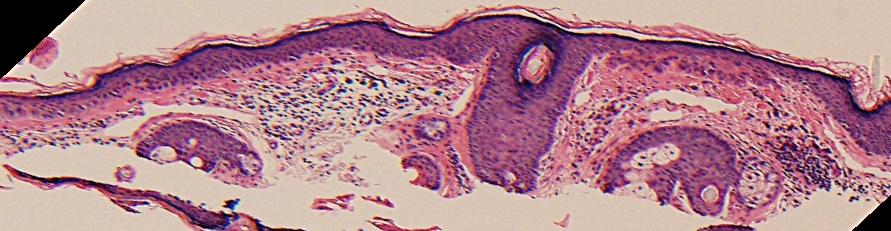

VA34: Right Temple, Actinic Keratosis, Hypotrophic, Focally reaching the base.

- White arrow denotes hair follicle

VA34: Right Temple, Adjacent, Normal

- Note normal hair follicle presentation